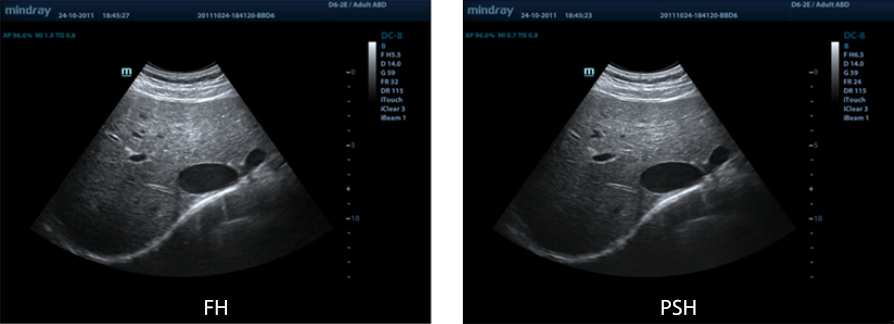

PSHITM (Imagen arm├│nica con inversi├│n de fase)

Las im├Īgenes arm├│nicas puras permiten suprimir los artefactos, generando menos ruido y aumentando la calidad de las im├Īgenes gracias a una mejor resoluci├│n de contraste.

FCI (adquisici├│n de la imagen por composici├│n de frecuencias)

Permite combinar diferentes frecuencias para formar una imagen de campo homog├®nea, lo que ofrece una penetraci├│n de imagen superior, especialmente para el escaneo de alta frecuencia.